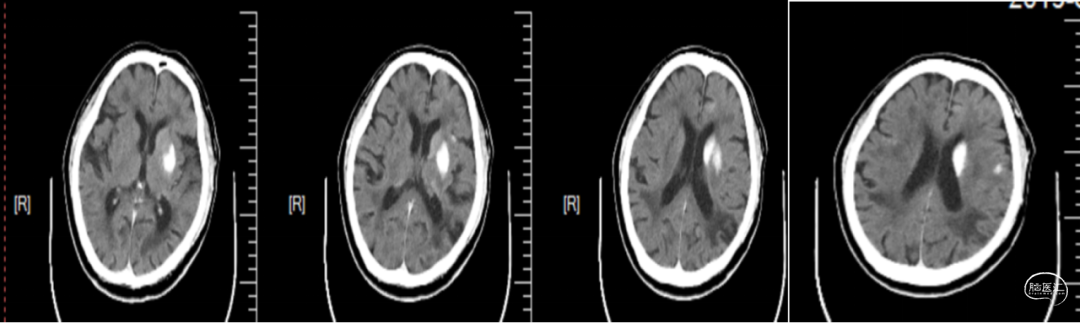

入院后头颅MRI评估提示:左侧额顶叶及侧脑室旁近期梗塞,见下图1。

图1.头颅DWI检查